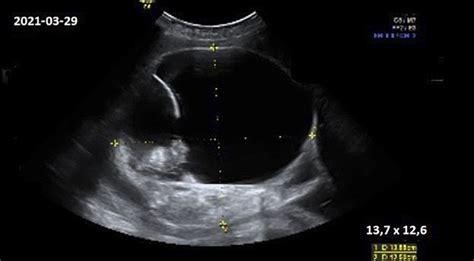

Šiuo metu vaikas jau yra 26-30 centimetrų ilgio ir sveria maždaug 500-600 gramų. Vaikas auga ypač greitai ir dabar jau galime kalbėti apie vaisiaus galimybę išgyventi ne įsčiose. Vis dėlto, tikimybė išgyventi ne jūsų kūne kol kas lieka labai maža. Tai lemia tai, kad kraujagyslės plaučiuose dar tik vystosi, o alveolės tvirtėja - tai būtina deguonies apytakai organizme. Plaučiuose taip pat pradeda gamintis medžiaga, neleidžianti sulipti alveolių sienelėms, o tai yra kritiškai svarbu kvėpavimui po gimimo. Šiame etape jau visiškai susiformavo vidinė ausis, atsakinga už kūno pusiausvyrą.